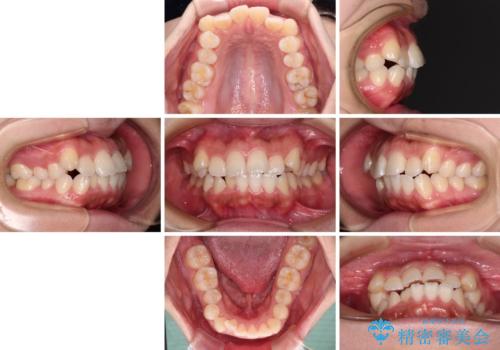

- 前歯の出っ歯と口元の閉じにくさを気にして来院された患者様です。

口元を積極的に引っ込めるために、上下左右の小臼歯4本を抜歯することとしました。

4本の歯を抜歯したことで、飛び出していた口元が引っ込み、横顔の印象が大きく改善されました。